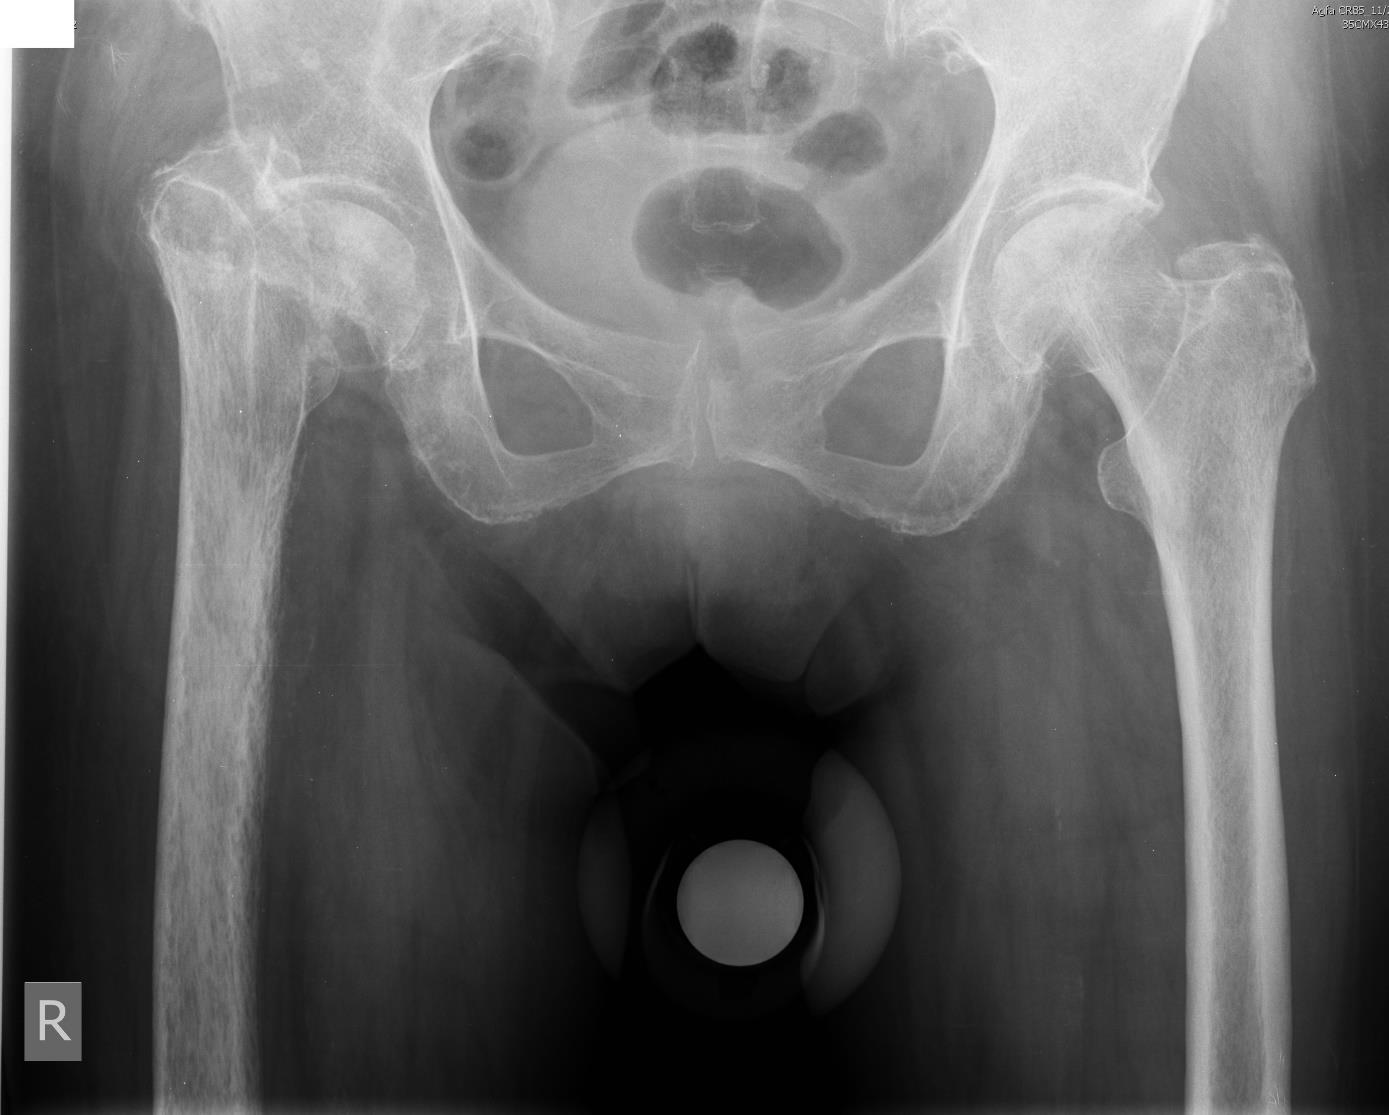

2) Proximal displacement of the right femur by radiography results was 2 cm, the piston test indicated the ease of lowering the femur, which was confirmed intraoperatively the length of the limb was restored without technical difficulties (Figure 3);

3) Medial displacement of the right femur required tissue mobilization to restore the hip offset. Scar tissues were diffusely bleeding during mobilization, and the achieved offset was assessed as a reasonable compromise between the intervention trauma and the restoration of ideal joint anatomy (Figure 3). The range of motion in the joint was full intraoperatively, without impingement;

5) Hypotrophy of muscles of the right thigh required most careful handling of soft tissues to avoid further aggravation of trophic disorders, and also to prevent postoperative hematomas, which was successfully realized. Hypotrophy of muscles enhances the risks of dislocation of the endoprosthesis, for which reason, an endoprosthesis with double mobility was installed (Figure 3).

Fig. 3. Postoperative plain radiograph of the pelvis of patient S.: correct position of endoprosthesis elements, uniform cement mantle, the length and offset of the femur almost completely corrected.